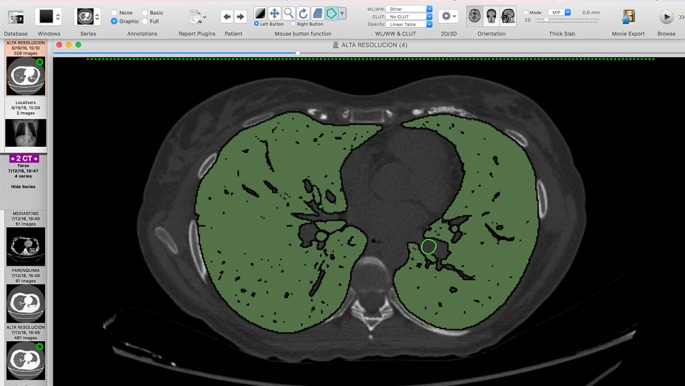

Bertolotti les envió las imágenes de la tomografía y, tras estudiarlas, lograron imprimir el modelo del bronquio en aproximadamente dos horas. El material que usaron es PLA y ABS, dos plásticos industriales de uso corriente.

“Entré al quirófano con una estrategia ya implementada, hacer una adecuada resección del tumor y reconstruir lo necesario sin comprometer al pulmón sano”, contó Bertolotti y advirtió que el modelo de plástico que fabricó el grupo de estudiantes desmintió varios “preconceptos” que tenía sobre la forma del tumor y que fue eso lo que le permitió salvarle el pulmón a la paciente. Además, explicó que si se logra extender la técnica, se disminuirán los riesgos y los tiempos quirúrgicos en beneficio del paciente.